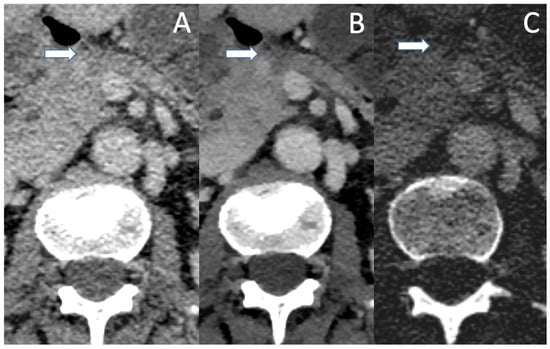

One of the most important factors in determining resectability is vascular involvement. The exact interpretation of tumor contact with the celiac trunk, the superior mesenteric artery, the common hepatic artery as well as the superior mesenteric vein and the portal vein is crucial for assessing the different categories of resectability, as stated in the NCCN criteria [52]. Differentiation between contact, abutment (<180° contact) and encasement (>180° contact) of the vascular structures can be challenging in conventional CT, especially in pretreated patients as mentioned above. VMI helps with improving lesion contrast, tumor margins in association with the vascular structures appear sharper and subtle opacifications of the vascular lumen become visible (see Figure 3 and Figure 4). In the detection of vascular invasion, conventional CT has a sensitivity and specificity of 94% and 82.4%, with no statistically significant differences in the diagnostic performances of conventional pancreas protocol CT and contrast-enhanced MRI [45,53].

Figure 3. Conventional (A), VMI (B) and ID (C) of a patient with locally advanced PDAC. In the conventional image, infiltration of the celiac trunk (marked by the arrow) could be assumed with irregular opacifications within the vascular lumen. Though VMI and ID show the abutment of the celiac trunk, there is no clear evidence of intraluminal infiltration as the vascular lumen shows a sharp contrast with no opacifications.

Figure 4. Conventional (A), VMI (B) and ID (C) of a patient with locally advanced PDAC (arrow). In VMI and ID, the lesion borders are well defined and the encasement of the AMS and the abutment of the VMS become more clearly visible.